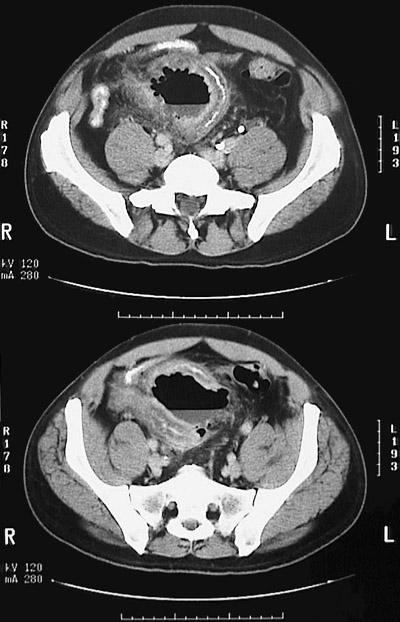

This abdominal CT scan reveals a partially loculated pelvic abscess with an air-fluid level that resulted from a ruptured diverticulum.